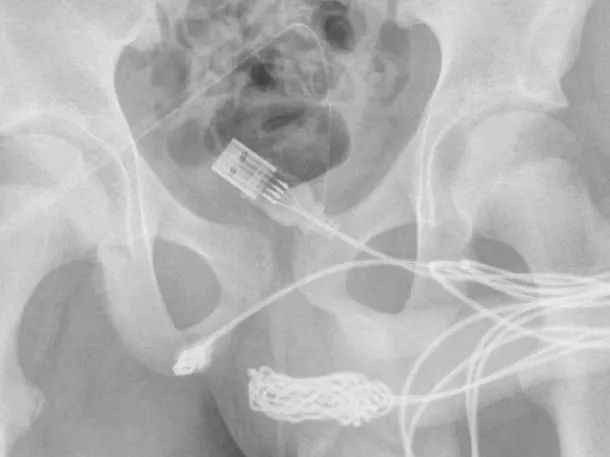

“Se descubrió que los dos puertos distales del cable USB sobresalían del meato uretral externo, mientras que la parte media del cable anudado permanecía dentro de la uretra”, indicaron los médicos en un informe difundido por ScienceDirect.com.

En un primer momento, los expertos buscaron extraer el cable del pene con una varilla de metal. Pero como había una gran cantidad de nudos en el cable, el paciente tuvo que ser operado.

Durante la cirugía para extraer el cable que tenía atrapado el joven en su pene, los médicos realizaron una inserción entre los genitales y el ano. De esa forma, lograron acceder al USB mediante los catéteres que habían colocado.

«Se realizó una incisión penoescrotal longitudinal sobre el cuerpo extraño palpable y se realizó una disección cuidadosa a través de los tejidos más profundos, dividiendo el músculo bulboesponjoso«, detallaron los expertos sobre el procedimiento insólito. Allí también destacaron que “ambos extremos del cable se sacaron con éxito a través del meato uretral externo”.